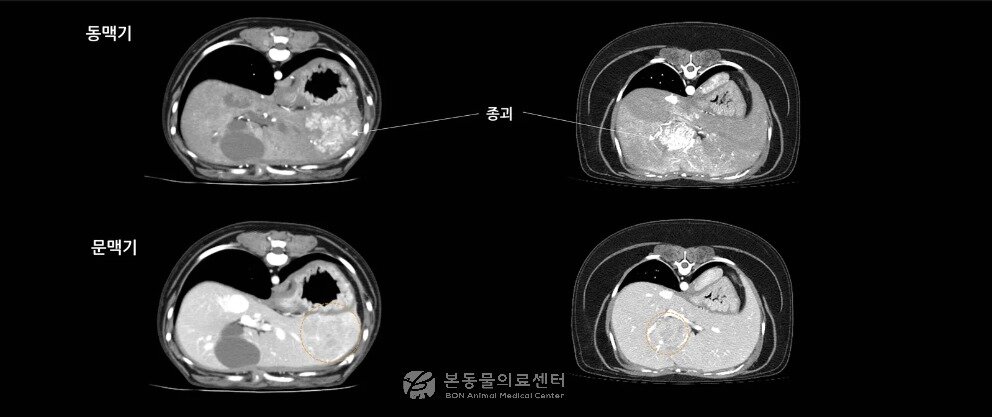

초음파와 CT 검사에서 매우 비슷한 소견을 보인 두 환견의 CT 영상(본동물의료센터 제공) ⓒ 뉴스1

초음파와 CT 검사에서 간 결절이 발견돼 매우 비슷한 소견을 보인 두 환견의 MRI 검사 결과. 한 환견은 악성 종양, 다른 환견은 양성으로 진단됐다(본동물의료센터 제공). ⓒ 뉴스1